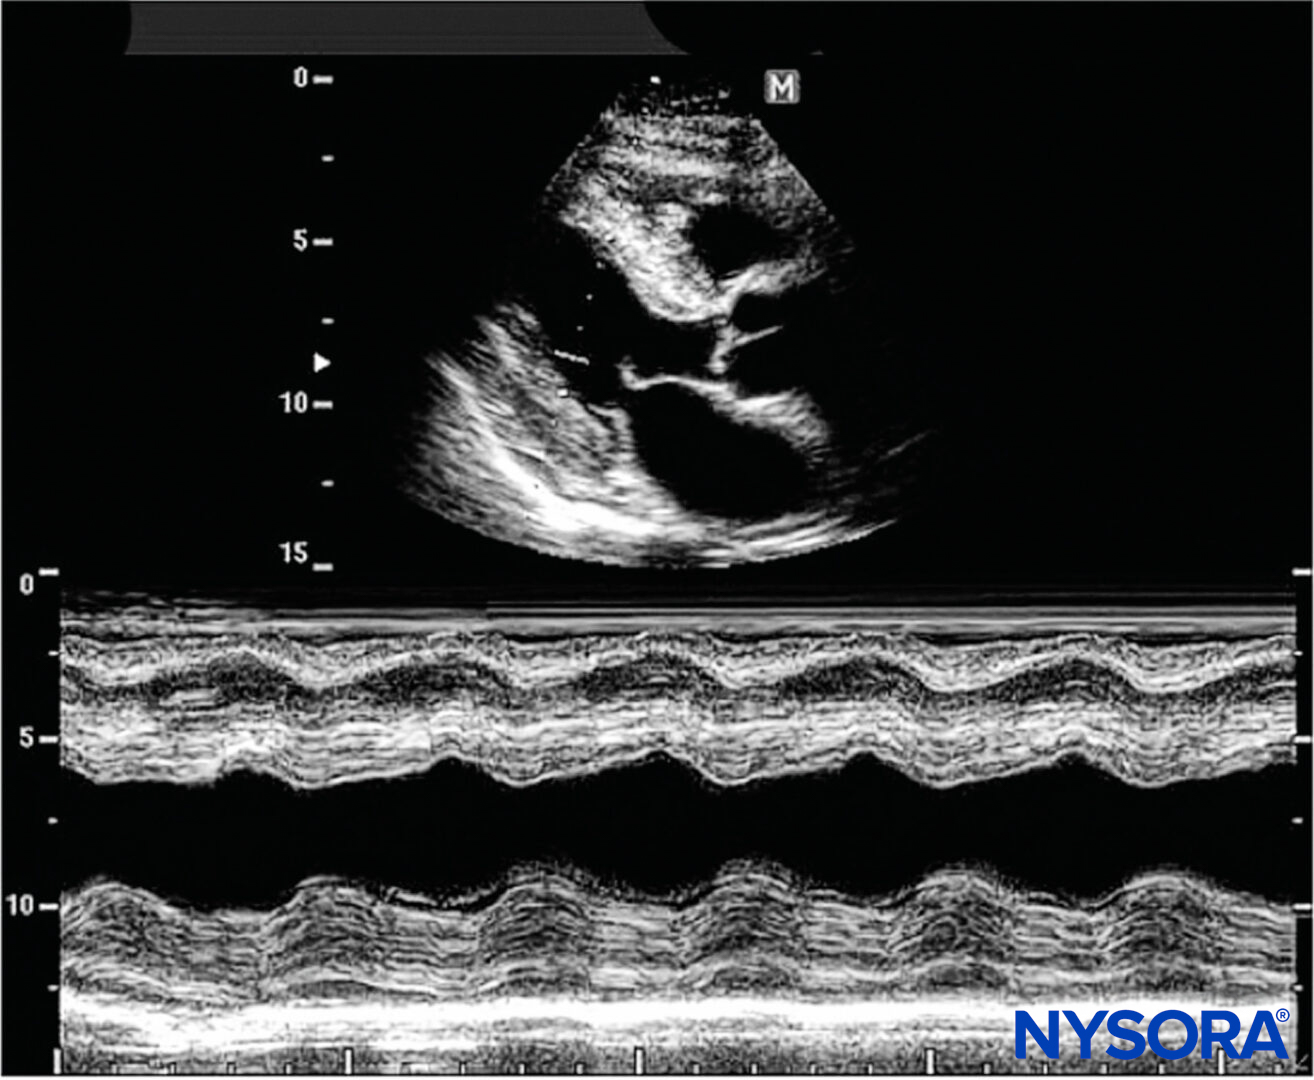

M-Mode

A single beam in an ultrasound scan can be used to produce a picture with a motion signal, where movement of a structure such as a heart valve can be depicted in a wave-like manner. M-mode is used extensively in cardiac and fetal cardiac imaging; however, its present use in regional anesthesia is negligible (Figure 16).

Figure 16. M-mode consists of a single beam used to produce an image with a motion signal. Movement of a structure can be depicted in a wavelike matter. (Reproduced with permission from Hadzic A: Hadzic’s Peripheral Nerve Blocks and Anatomy for Ultrasound-Guided Regional Anesthesia, 2nd ed. New York: McGraw-Hill, Inc; 2011.)